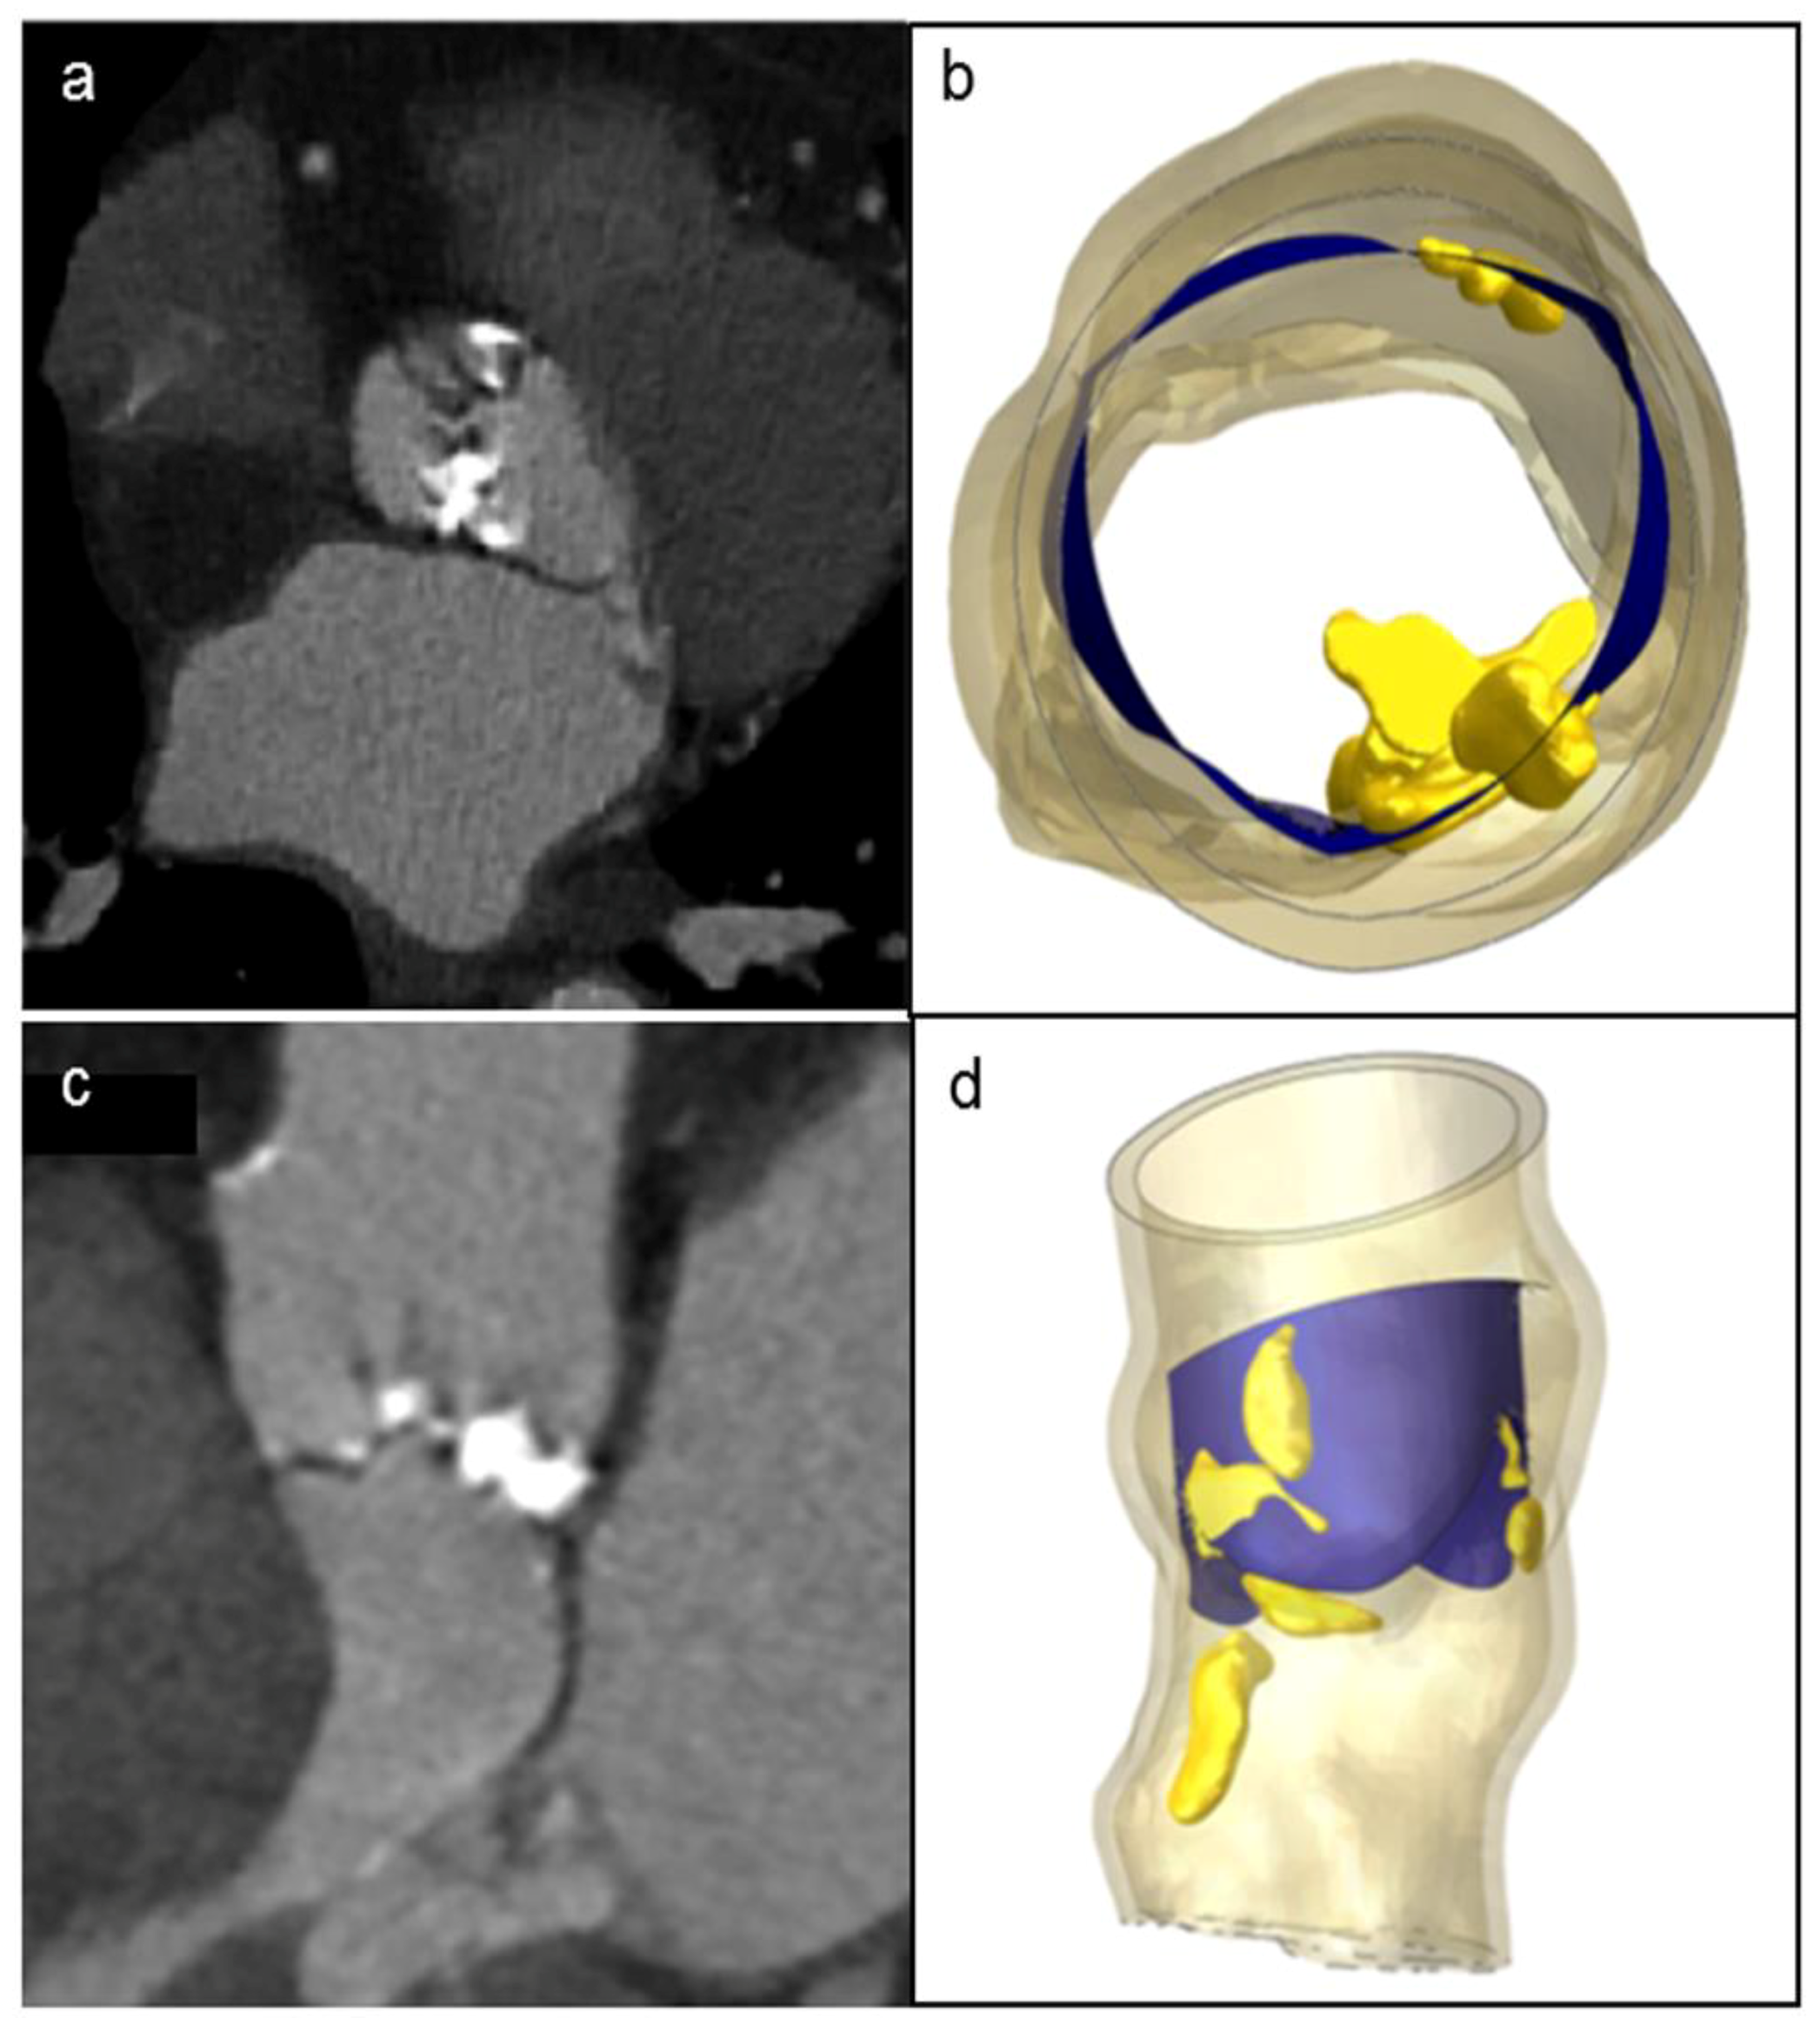

3.2. Localization and Evaluation of Paravalvular Leakage